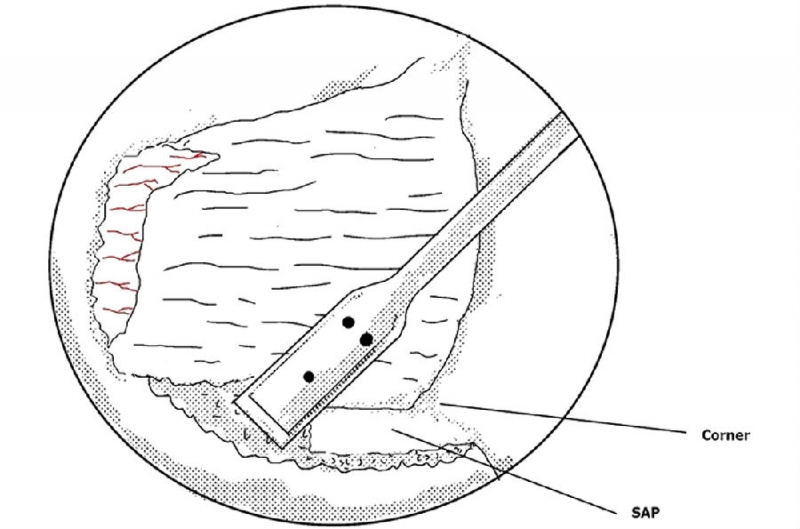

6. 使用骨凿将磨薄的下关节内缘凿除显露Corner和上关节突内缘;

7. 使用反向的椎板咬骨钳减压同侧Corner部位;

8. 减压的外界参考椎弓根内壁;

延伸阅读:UBE同侧侧隐窝减压范围的问题

UBE处理椎管狭窄病例时,对于侧隐窝狭窄的患者,同侧减压范围与椎弓根内缘平齐即可。

从标本上看,椎弓根其实就位于终板的下方,这是术中判断椎弓根位置的解剖标志。

与椎间盘的下缘平齐即是椎弓根的上缘。

去除部分椎板上缘骨质尤其是与上关节突结合的部位利于黄韧带的切除及椎弓根内壁的显露。这个部位显露神经根的风险最小。